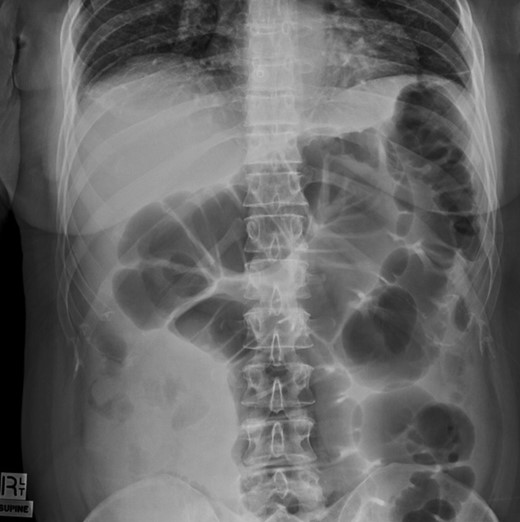

Colonoscopy revealed melanosis coli, diverticulosis and grade four hemorrhoids. She was admitted overnight following haemorrhoidectomy. The following morning she complained of abdominal pain, which she described similar to diverticulitis, and she was tender on exam. To rule out perforation, a plain film abdomen was performed. Findings were suggestive of gaseous distension following colonoscopic air insufflation without evidence of free gas (Fig. 1). Watchful waiting approach was adopted, however the patient deteriorated further during the course of the day. She had a vasovagal episode with tachycardia (134 bpm) and hypotension (67/47 mmHg). A venous blood gas revealed lactate level of 7 mmol/l. She underwent an urgent CT with findings suggestive of pericaecal internal hernia with the ileal loops located in the right paracolic gutter demonstrating features of ischemia (Fig. 2). There was moderate amount of free fluid, but no free gas to suggest perforation (Fig. 3). She was taken to theater that day for emergency laparotomy. The intraoperative findings included two litres of bloodstained fluid and floppy cecum with a band of adhesion to its own mesenteric base, probably adhesional having developed after the appendicectomy. This band has created a window through which three quarters of her small bowel had herniated and became strangulated. The bowel looked very ischemic, but not necrosed. The surgeons divided the adhesion, untwisted the small bowel and waited 20 minutes to allow sufficient time for bowel ischemia to recover. Fortunately, she did not require any bowel resection.

Plain film of abdomen showing colonic gaseous distension following colonoscopy.